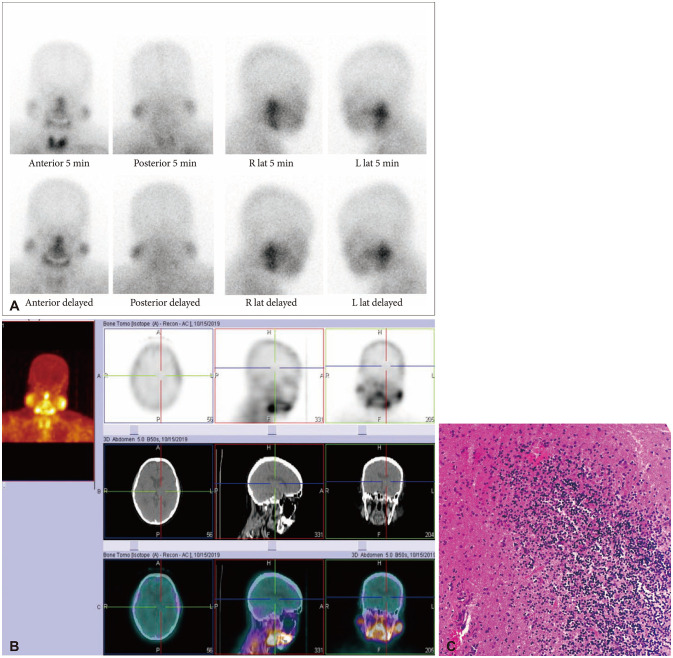

Background: Thallium-201 single-photon emission computed tomography/computed tomography (SPECT/CT) brain scan is an imaging modality which can be done to differentiate between malignant and nonmalignant lesions among patients with nonconclusive findings on conventional neuroimaging. This study describes the results of thallium-201 SPECT/CT brain imaging and relate it to histopathologic and/or clinical findings and evaluate the value of thallium-201 SPECT/CT brain imaging in differentiating malignant from nonmalignant lesions.

Methods: This is a retrospective case series study of 10 patients with cerebral lesions who underwent thallium-201 SPECT/CT brain imaging in a hospital in the Philippines from 2010 to 2021.

Results: A total of 10 patients underwent thallium-201 SPECT/CT brain scan. Six had negative results while 4 had positive results. All of the patients who had positive results were found to have malignancy, whether recurrent or newly diagnosed. All of the patients with negative scan were found to have either an infectious and inflammatory disease and responded to treatment albeit in different degrees. Two of the 10 patients underwent biopsy whose results were consistent with the thallium-201 SPECT/CT brain scan results.

Conclusion: Thallium-201 brain scan combined with SPECT and SPECT/CT has been demonstrated to be useful in distinguishing malignant from nonmalignant lesions and is more cost-effective versus other imaging techniques. The findings in this study support the role of thallium scintigraphy in the diagnosis of patients with brain lesions most significantly when there is a need to differentiate between a malignant and benign condition.